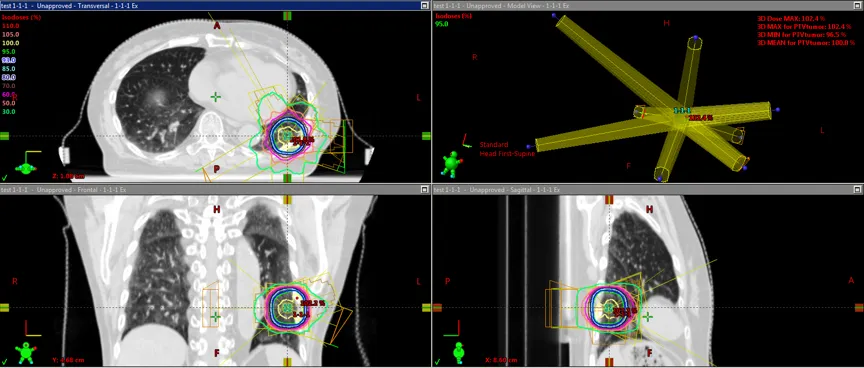

SBRT(Stereotactic Body Radiotherapy)とは、

体幹部の腫瘍に対して高精度に強い放射線を少ない回数で照射する放射線治療です。

高精度照射

SBRTでは

・CT

・MRI

・画像誘導放射線治療(IGRT)

を用いて腫瘍の位置を正確に確認しながら照射します。

そのため

正常組織へのダメージを最小限に抑えることができます。